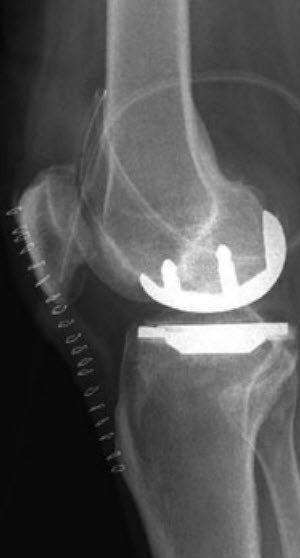

Ist von der Abnutzung nur der Kniescheibenteil oder der innere oder äussere Teil des Kniegelenks betroffen, kann ein teilweiser Gelenkersatz (Schlittenprothese / unikompartimentelle Kniearthroplastik) eingesetzt werden. Wichtige Voraussetzungen für die Indikation sind, dass sich die Arthrose hauptsächlich auf einen Abschnitt des Kniegelenks beschränkt und dass die Kniebänder noch funktionell sind.

Eine Teilprothese bietet im Vergleich zur Totalprothese grösstenteils eine bessere Beweglichkeit sowie ein natürlicheres Kniegefühl. Der Eingriff ist ausserdem weniger invasiv, da alle Bandstrukturen und die noch gesunden Gelenkteile erhalten bleiben, was die rasche Erholung nach der Operation begünstigt.

Das Kniegelenk muss dazu vorn durch einen Hautschnitt von ca. 15 cm Länge eröffnet werden. Die abgenutzten Gelenksoberflächen werden nach einem speziellen Schnittplan bearbeitet und so für den künstlichen Oberflächenersatz vorbereitet. Die exakte Grösse und die Art der Prothese werden anhand der präoperativen Röntgenbilder und der Vermessung während der Operation ausgewählt. Das Kunstgelenk wird anschliessend meist mit Knochenzement im Knochen verankert.